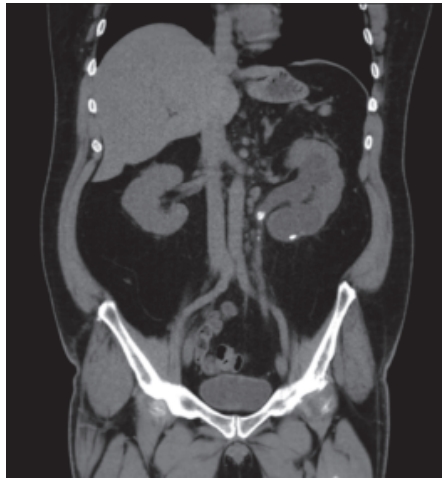

Nos exames de imagem do abdome, a visualização dos principais órgãos, incluindo localização, morfologia e densidade, é muito importante para a elucidação diagnóstica.

O tecnólogo em radiologia que atua na área do diagnóstico por imagem, ao realizar um exame dessa região, precisa certificar-se de que a imagem contempla todas as áreas de interesse.

Assim, o campo de visão deve incluir as estruturas que vão desde o diafragma até a sínfise púbica. A figura a seguir retrata uma tomografia do abdome, evidenciando os órgãos da região.

Com base na imagem e em seus conhecimentos sobre fisiologia, anatomia e quadrantes abdominais, avalie as afirmações a seguir.